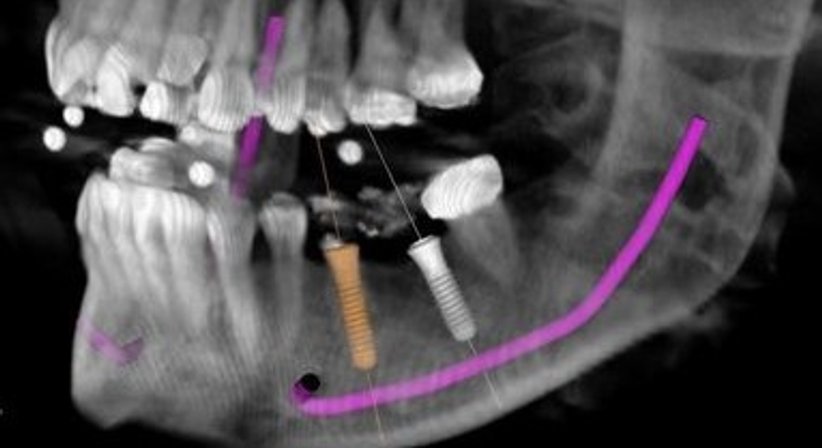

Die Praxis ist mit einem digitalen 3D Röntgen ausgestattet (digitale Volumentomographie, DVT).

Neben klassischen Implantationstechniken bieten wir Patienten die computergestützte Implantationstechnik an. Hierfür wird der Knochen dreidimensional dargestellt, was es ermöglicht, den Zahn virtuell in die ideale Position zu stellen und das Implantat in dieser zu planen. Dadurch wissen wir bereits vorab, ob an der jeweiligen Implantationsstelle ausreichend Knochenmaterial in guter Qualität vorhanden ist.

Dank computernavigierter Implantologie können Implantationen sehr genau und vorausschauend geplant werden, das vorhandene Knochenangebot wird optimal genutzt und ein Knochenaufbau kann in einigen Fällen vermieden werden.